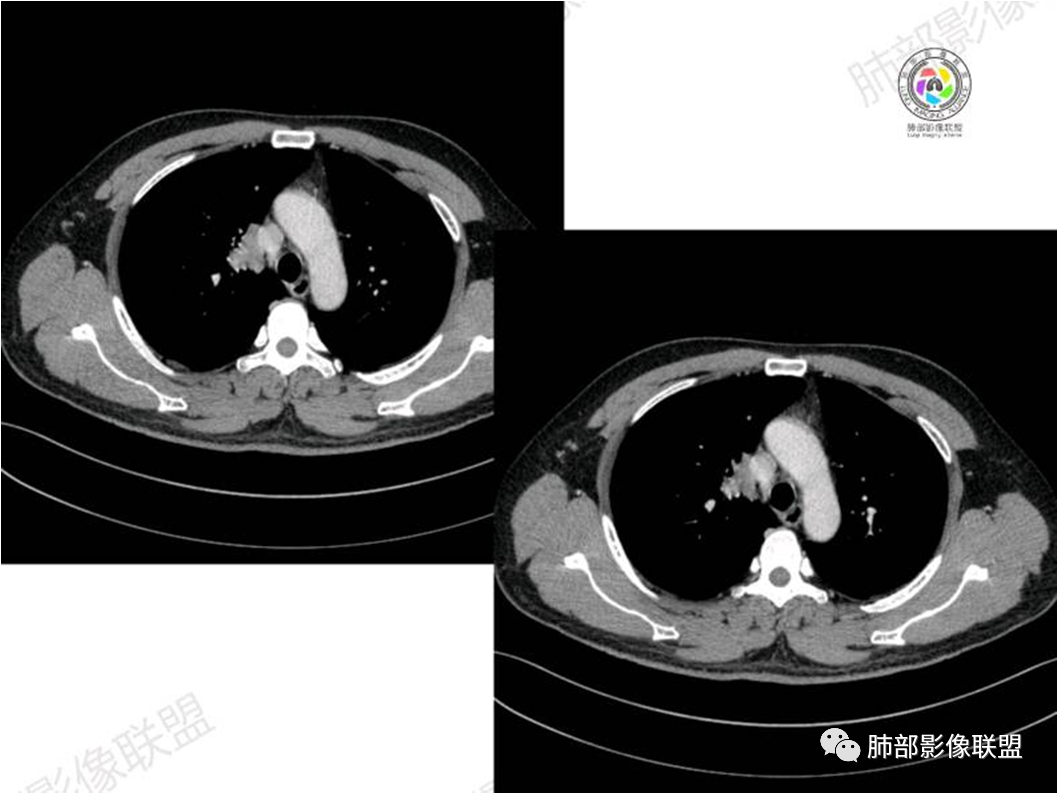

中年男性,偶有咳嗽,右肺上叶近纵膈旁占位,内可见僵硬的支气管和小空泡征,病灶边缘可见分叶,毛刺,增强病灶中度以上不均匀强化,可见血管造影征,考虑恶性病变,腺癌可能性大。

右肺上叶纵隔胸膜侧一实性肿块,与纵隔胸膜宽基底相连,局部脂肪间隙消失,形态欠规则,内部可见多个小空泡,平扫密度尚均匀,增强后可见点条状强化,内部穿行血管,周围肺组织干净,纵隔淋巴结略肿大,男性44岁,只有咳嗽,考虑恶性肿瘤,腺癌,鳞癌。鉴别结核,OP,炎性假瘤。

右肺上叶近纵膈旁肿块,密度均匀,边缘分叶,毛刺,气管受压变窄,不均匀强化,可见血管造影征,考虑淋巴瘤,鉴别炎性假瘤。

中年男性,右肺上叶纵隔旁软组织肿块,边缘膨隆、毛糙,可见多发分叶,支气管穿行,部分截断,增强后密度欠均匀,纵隔内见多发小淋巴结,首先考虑恶性,腺癌,鉴别淋巴瘤

中年男性,右肺上叶纵隔旁肿瘤,稍膨隆,有毛刺,支气管穿行,远端闭塞,强化均匀,血管走行尚可,考虑淋巴瘤可能性大(支气管远端闭塞,不太符合),鉴别腺癌(气管穿行后闭塞,不太符合),op(病灶稍膨隆)

患者中年男性,咳嗽就诊,无其他不适。胸部CT:右肺上叶尖段上纵膈旁肿块,边界清楚,边缘光滑,内见支气管受压变窄,伴阻塞性改变,增强均匀强化,见血管造影征。综合考虑恶性病变,小细胞肺癌或淋巴瘤。气管镜活检应能明确。

④血管造影征是另一 点,强化的肺血管形态及走行正常,无扭曲或增 粗,其病理学基础为肿瘤细胞沿间质增生浸润,不破坏血管或支气管,病灶内肺支架结构完整,本研究发现率为75%;

⑤病灶多为中度强化,部分轻度强化;